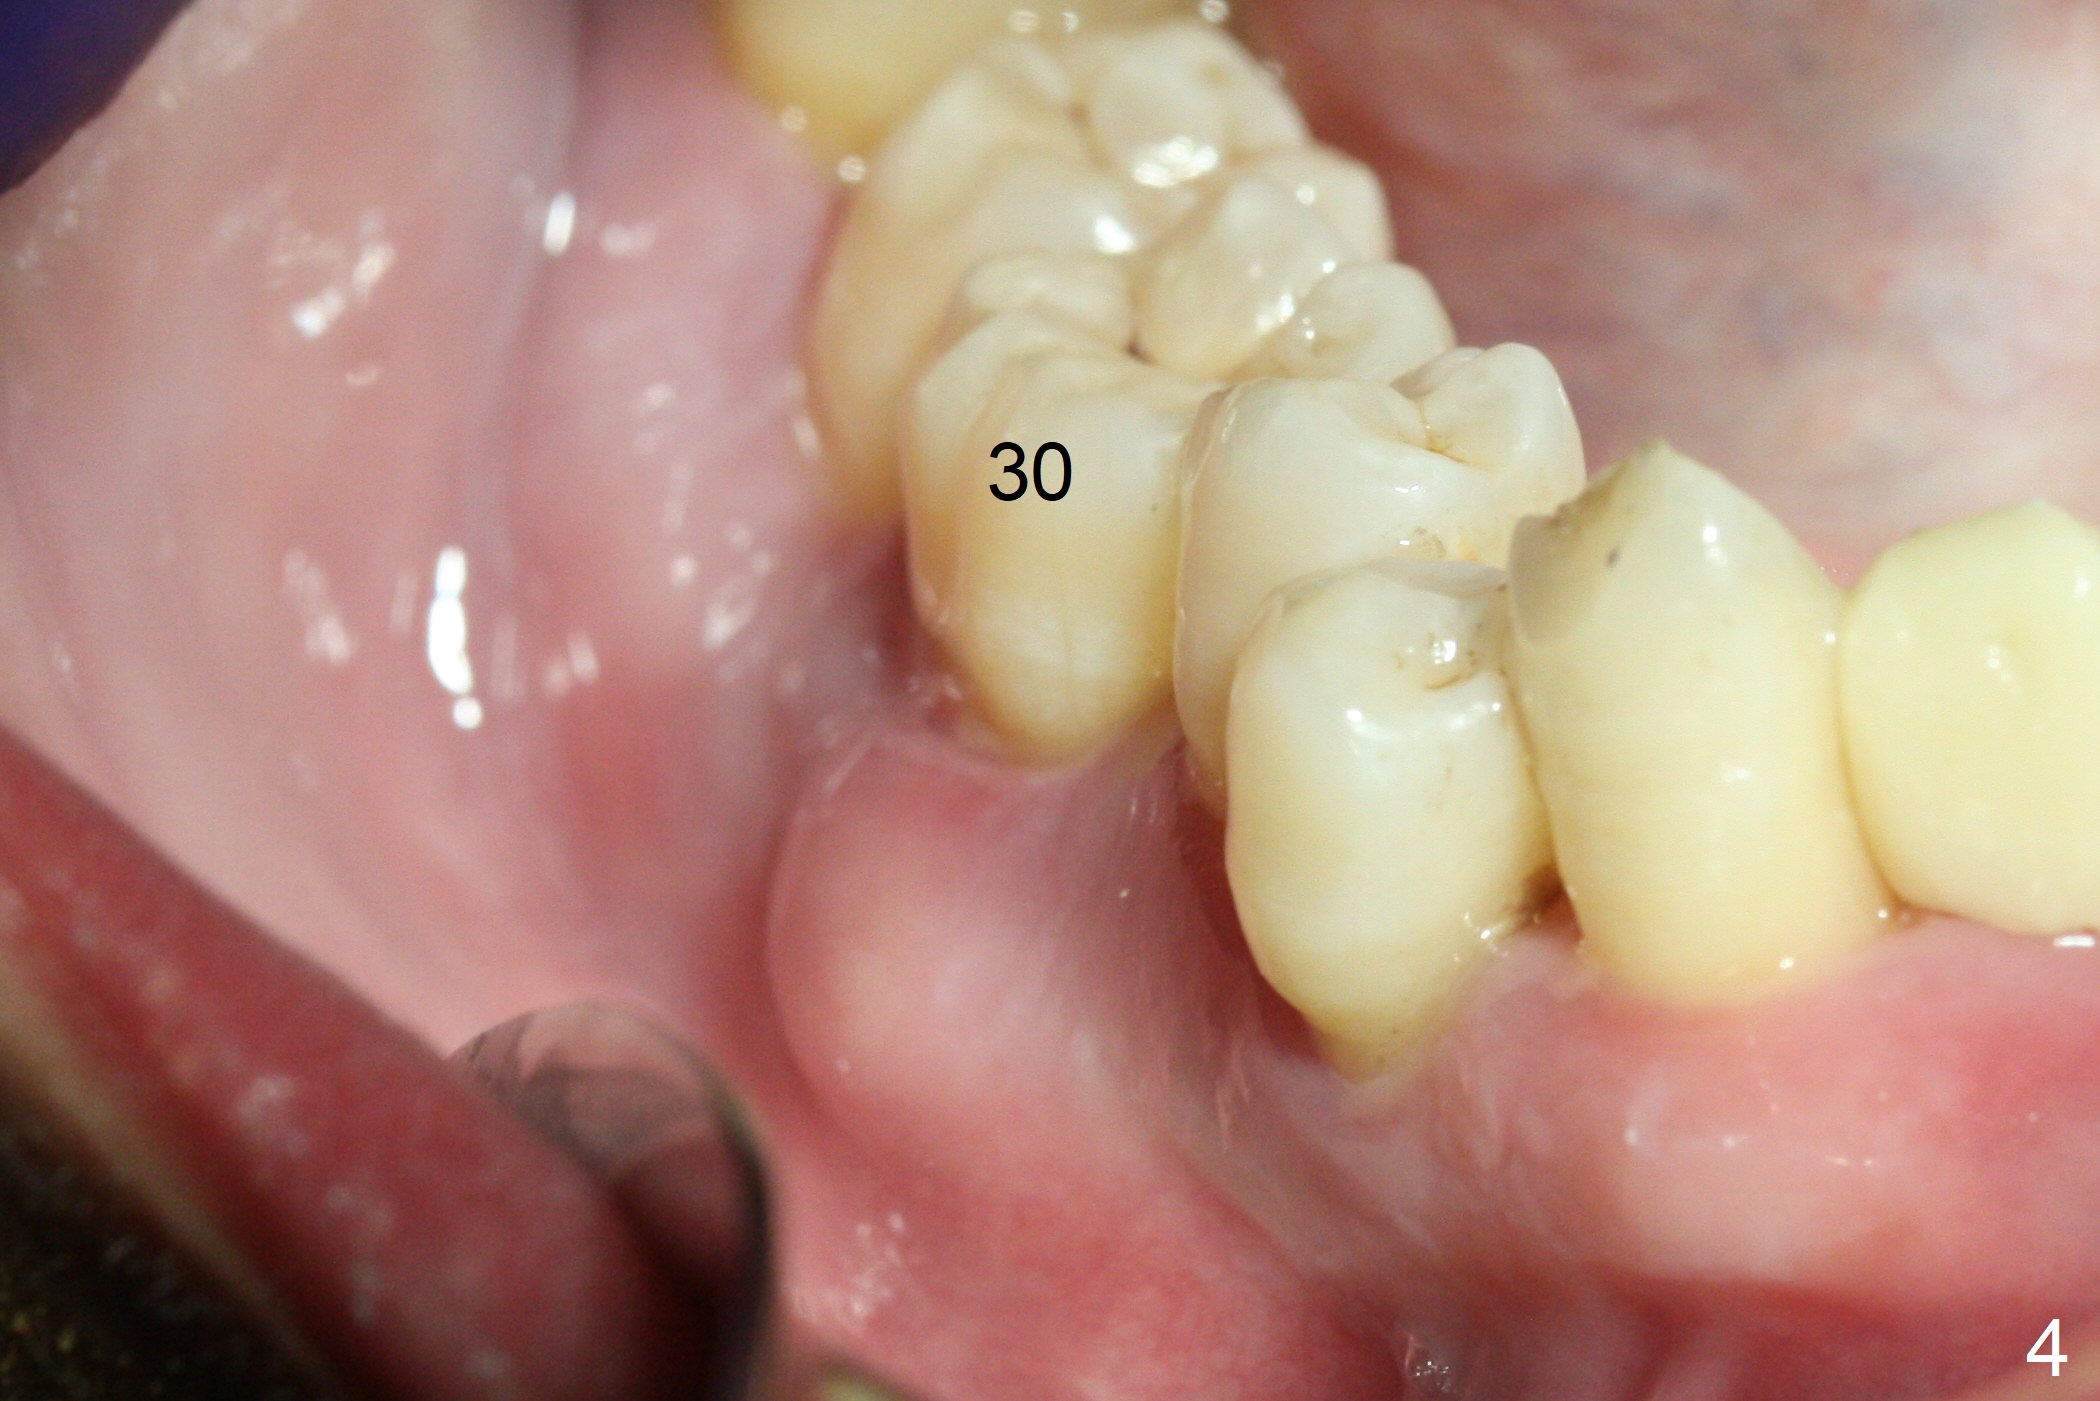

The 36-year-old man (ex-smoker, quit for 4-5 years) insists upon #3 and 5 extraction first for implants, in spite of more severe infection at #7, 14,19,30 (Fig.1-4). The gingiva around #23-26 implants is healthy 3 weeks postop (Fig.5). The initial depths at #3 and 5 are 8.5 mm (bone-level) and 18 mmm (gingiva-level (13 mm (implant length) + 5 mm cuff), respectively. When a drill penetrates the sinus floor, confirm the depth. After use of 3.8 mm drill, 4.5 mm tap drill is inserted at #3 without stability, while a 4.5x13 mm implant is placed at #5 with primary stability (Fig.6,7). Then a 5x11.5 mm is placed at #3 subcrestal proximally after sinus lift with Vanilla graft (without sinus membrane perforation; Fig.8). The implant at #5 is seated ~1 mm deeper (subcrestal mesially (^^); supracrestal distally (^)); allograft is placed around the implants prior to insertion of 6.5x7(5) and 5.5x4(5) mm abutments; last more allograft is added (Fig.9 *, 10). The implants seem to have been osteointegrated 4.5 months postop (Fig.11,12). The gingiva is healthy around the implants without bone loss 3 months post cementation (Fig.13,14).